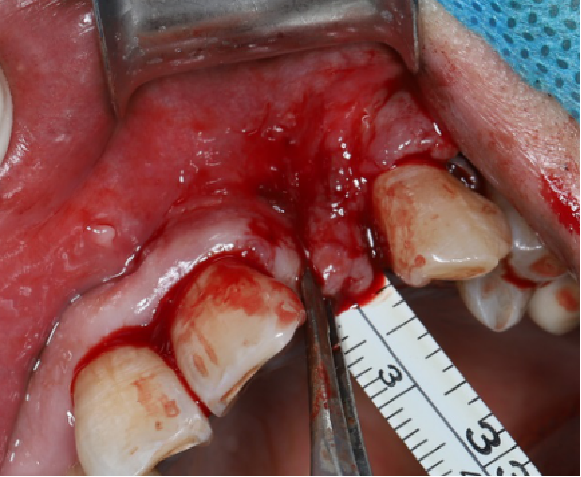

采用不切开骨膜的软组织扩张术——Soft Tissue Extend释放软组织张力

记录翻瓣后原始软组织瓣长度,使用软组织搔刮器(Soft Tissue Extender)冠根向搔刮软组织瓣。

在不切断骨膜的前提下,使用软组织刮治器反复搔刮软组织瓣,可以起到延长软组织瓣的作用。

使用软组织搔刮扩张前后对比:可见在不切断骨膜的前提下,使用软组织搔刮即可获得软组织瓣延长8-9mm。